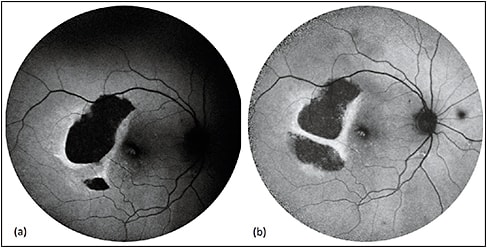

As a well-known complication of AMD, RPE tears present as a wedge- or crescent-shaped area of remarkable hypoautofluorescence with sharp, irregular borders representing the zone of denuded RPE, and adjacent hyperautofluorescence at the site of rolled retracted RPE (Figure 1). Over time, RPE tears undergo resurfacing, with recovery of autofluorescence and associated visual function occurring centripetally toward the center of the lesion (Figure 2).15-18

Figure 1. Sequential FAF of RPE tear. RPE tears (a) appear as well-demarcated central hypoautofluorescence due to absent RPE with adjacent irregular hyperautofluorescence corresponding to the retracted edges of RPE. Serial images obtained three weeks (b) and one year (c) later show resurfacing and remodeling of the lesion, with centripetal recovery of autofluorescence extending from the borders.

COURTESY OF BIOMED CENTRAL.